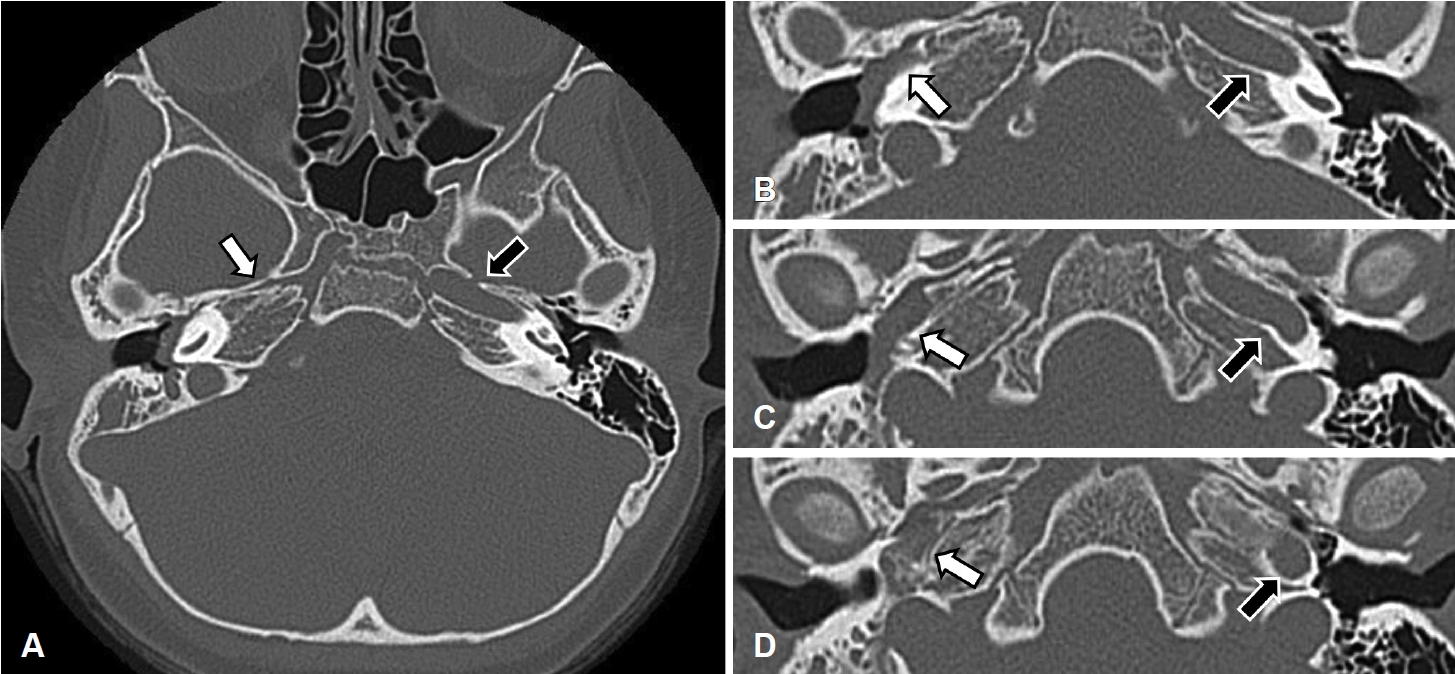

Fig. 2.

The images of temporal bone CT. Axial images at the level of skull base are presented from superior (A) to inferior (D). The images show an absence of ICA at right side (white arrow) and an presence of normal ICA at left side (black arrow). Consecutive axial images from (B) to (D) show the soft tissue density lesion at right middle ear occupying the space where ICA should have been. ICA: internal carotid artery.

측두골 전산화단층촬영에서 우측 중고실, 하고실 전체와 이관의 입구부를 침범한 연조직 밀도의 병변이 관찰되었고 이소골 연쇄는 정상이었다. 동측 측두골 추체부에 내경동맥관이 결손되어 있었고, 중이 병변은 내경동맥 결손 부위 공간을 채우고 있었다(Fig. 2). 병변이 상고실을 제외한 중이강 전체를 침범하고 있으나 골결손과 이소골 연쇄의 손상이 없는 점에서 진주종이 아닌 다른 연부조직 종양 가능성이 제기되어 자기공명영상을 시행하였다.